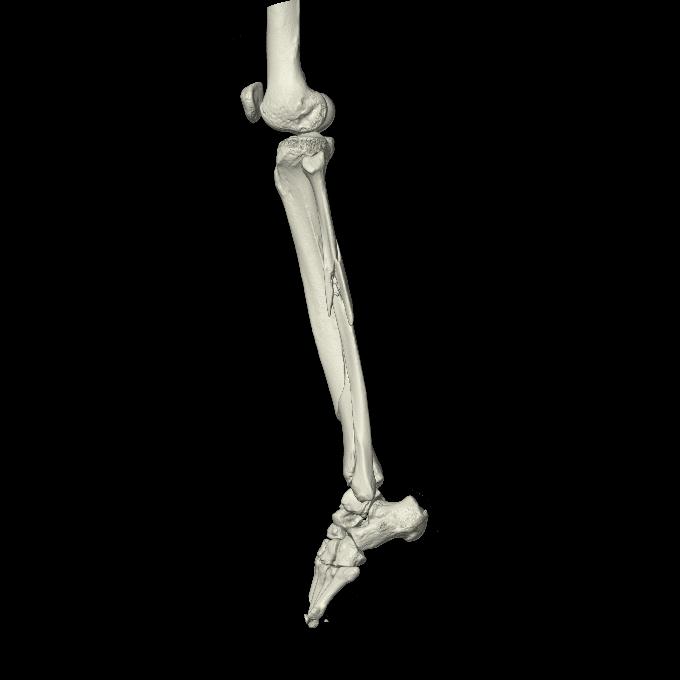

102803 1/12(キウスなし) 1/27 左下腿 4R 30歳女性 左脛骨軸内釘